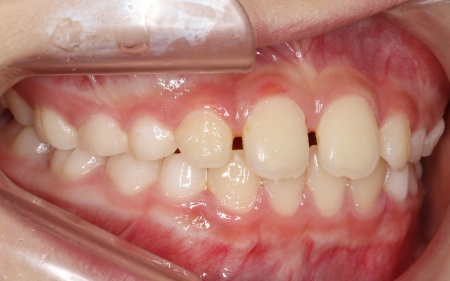

治療前

診断結果 拝見したところ、患者様は乳歯のみが生えている乳歯列期の段階でしたが、この時点ですでに反対咬合が認められました。

反対咬合とは、下の前歯が上の前歯よりも前に出ている状態のことで、一般的に「受け口」とも呼ばれます。